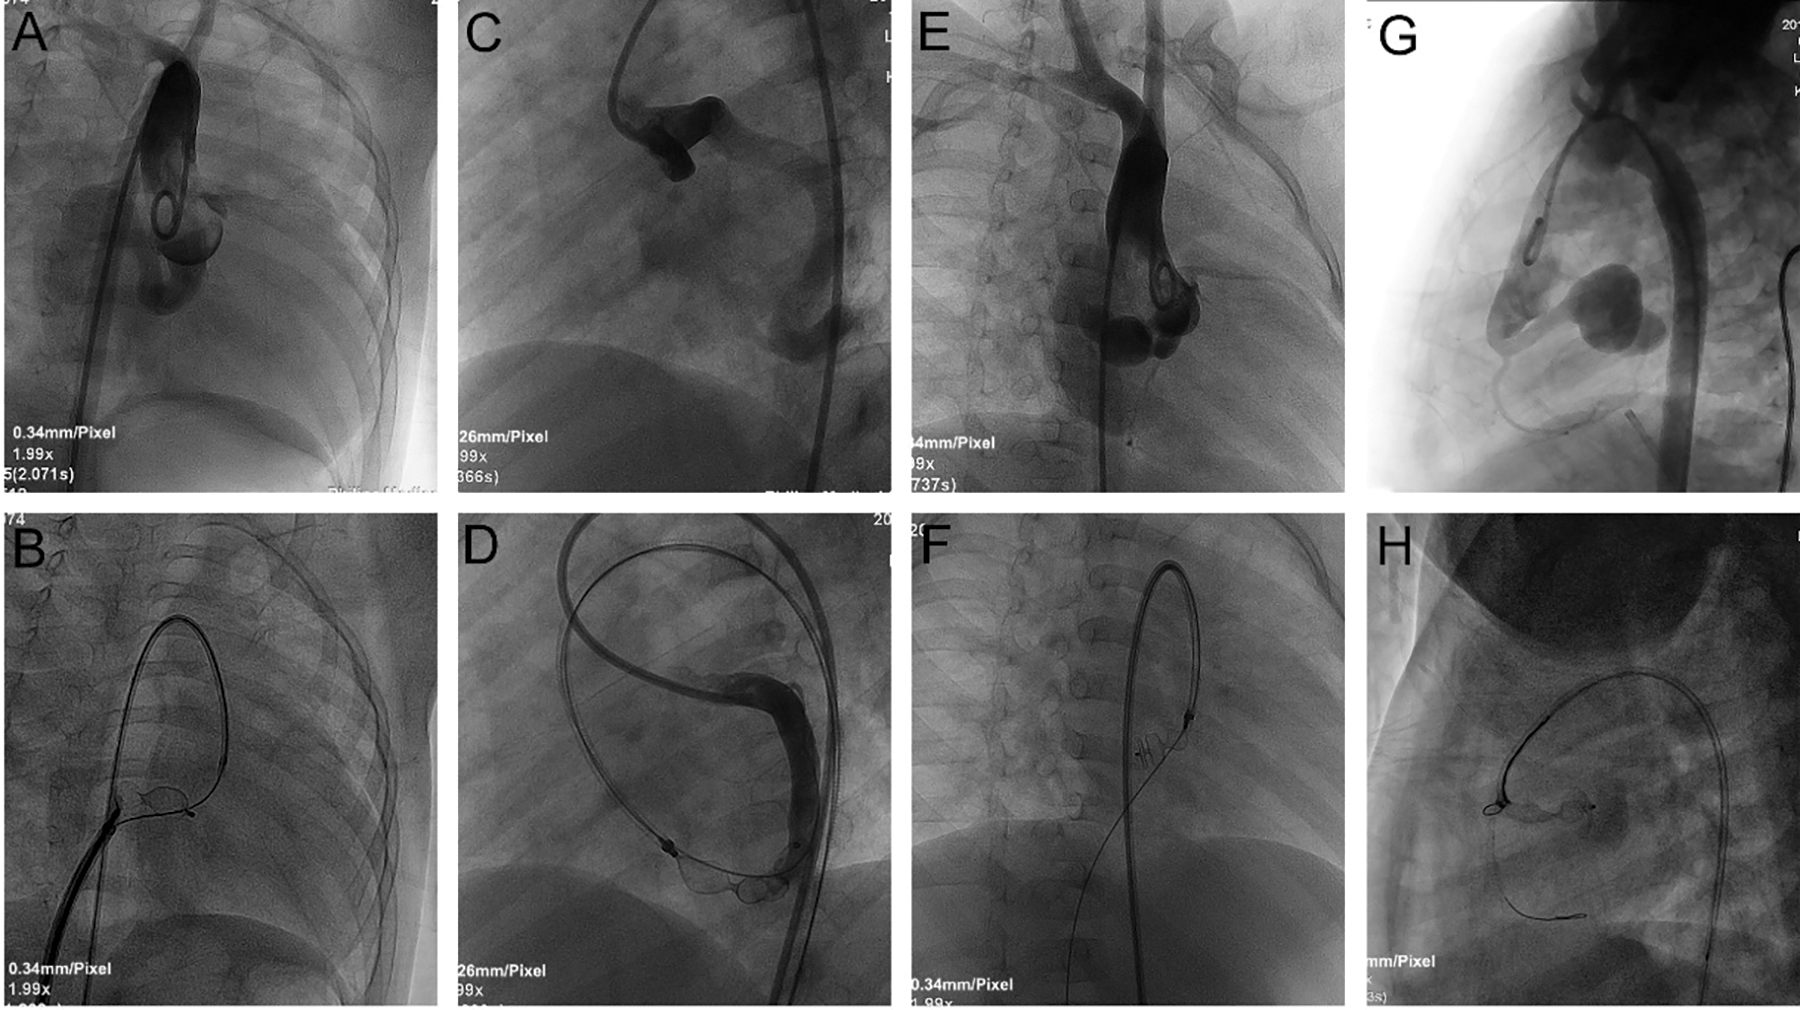

Details of TCC are summarized in Table 3. During procedure, antegrade venous/arterial or retrograde arterial approach after the A-V/A-A loops was used in 53 cases (80.3%), and retrograde arterial approach was used in 13 cases (19.7%, Fig. 3). The CCFs were occluded at the proximal site in 22 patients (33.33%), at the distal site in 42 patients (63.64%), and at both sites in 2 patients (3.03%, Fig. 4). Types of devices used in the closure procedure are presented in Table 3. PDA occluder was most commonly used (27.3%), followed by AVP II (22.7%), and VSD occluder (mainly muscular VSD occluder) (16.7%).

Figure 3: TCC of CCFs using different approaches. A, B: Ascending aortogram in RAO 30° projection demonstrated an RCA-to-RA fistula. An 8 mm VSD occluder was deployed through the antegrade venous approach via an A‑V loop. C, D: Ascending aortogram in LAO 45° projection demonstrated an LCX-to-LV fistula. A 12 mm AVP II was deployed through the antegrade arterial approach via an A-A loop. E, F: Ascending aortogram in RAO 45° projection demonstrated an RCA-to-RA fistula. A 9 mm AVP II was deployed through the retrograde arterial approach via an A-V loop. G, H: Ascending aortogram in LAO 90° projection demonstrated an RCA-to-RA fistula with a giant CAA. A 5/6 mm ADO II was deployed through the retrograde arterial approach

Notes: TCC: transcatheter closure; CCF: coronary cameral fistula; RAO: right anterior oblique; RCA: right coronary artery; RA: right atrium; VSD: ventricular septal defect; A-V loop: arterio-venous loop; LAO: left anterior oblique; LCX: left circumflex coronary artery; LV: left ventricle; A-A loop: arterio-arterial loop; AVP II: Amplatzer vascular plug II; CAA: coronary artery aneurysm; ADO II: Amplatzer duct occluder II